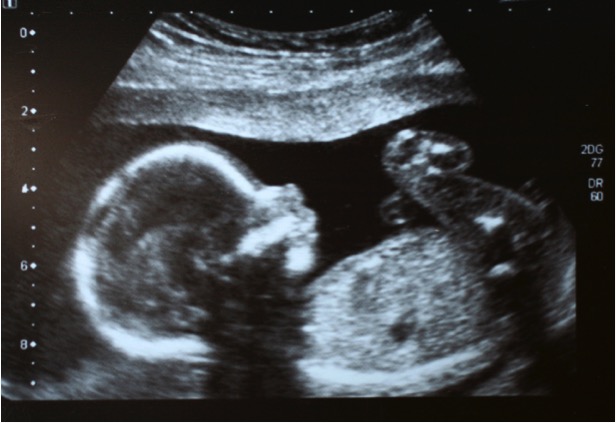

Once inside, Jill says the clinic kept everything very impersonal. She explains that the “counseling” consisted of two quick questions, and then a sigh, followed by the response, “Well, it’s decided then.” She was shown a movie on the abortion procedure which she describes as “extremely clean, like almost stick figures.” An ultrasound was performed, but Jill wasn’t allowed to see any of it.

But as she went up to pay prior to the procedure, God sent a sign to confirm Jill’s reservations over having the abortion. She was never supposed to see the picture from the ultrasound of her son, but there it was in plain sight. One of the clinic staff had mistakenly left it sitting on top of Jill’s file, and once she saw her baby’s little arms, legs and head, she knew she couldn’t go through with taking his life.